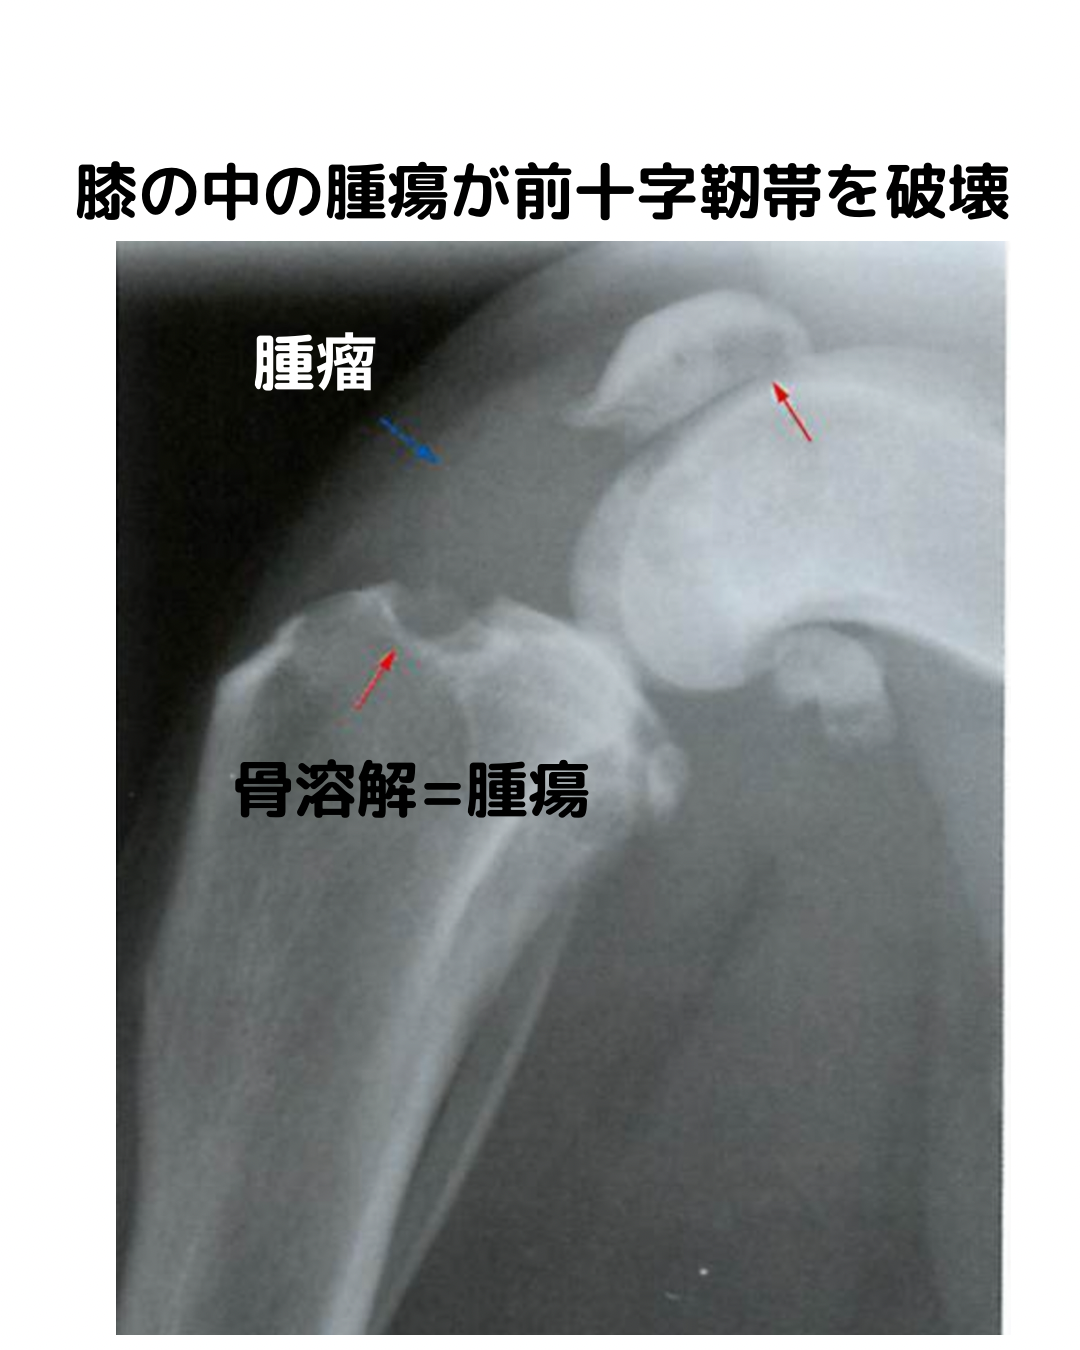

腫瘍・感染のレントゲン鑑別(ここを漏らさない)

赤旗:“痛みの割に不安定性が弱い/骨破壊が急/関節をまたぐ病変”。

B. 滑膜由来腫瘍(関節を越えるのが特徴)

• 滑膜肉腫/滑膜細胞肉腫:関節周囲軟部腫瘤+骨端の“バルーン状溶骨”、しばしば両骨の関節面側を侵す。関節液多量。

• 組織球性肉腫(periarticular HS):大型犬、重度の関節腫脹と骨端の侵食。

次の一手:赤旗があれば超音波で軟部腫瘤確認→FNA/生検、あるいはCT/MRI

“不安定性が典型でない膝+攻撃的骨変化”は必ず腫瘍鑑別を。